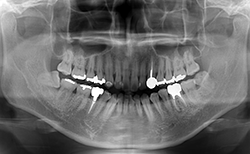

図❷ 初診時のパノラマX線写真

画像所見:パノラマX線写真(図❷)にて、32周囲骨に骨吸収など、あきらかな異常所見を認めなかった。